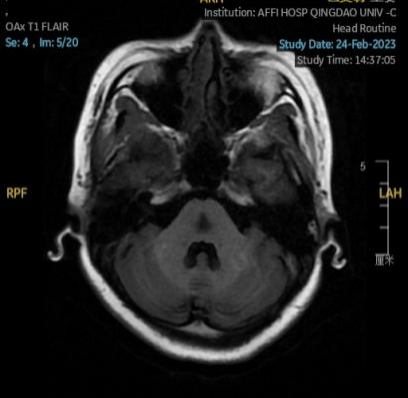

2023.01.18颅脑MR平扫示双侧基底节区及桥脑异常信号,考虑渗透性神经脱髓鞘综合征可能,见图1。

图1 2023.1.18颅脑MR成像示双侧基底节区及桥脑见对称性片样长T1长T2信号,FLAIR呈高信号。脑室、脑池、脑沟、脑裂未见明显异常。中线结构居中。小脑、脑干未见明显异常信号。